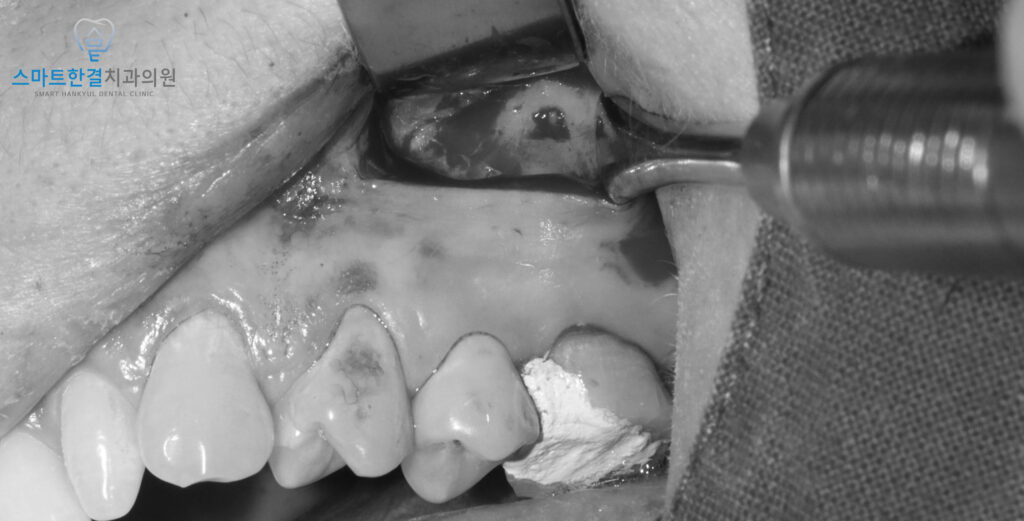

재신경치료를 진행하면서,

치근단절제술을 진행하였어요.

치료를 위해 잇몸을 열어보니,

치아의 뿌리 끝 부분에서

고름이 나오는 것을 확인할 수 있었어요

이 고름은 염증이 생긴 부위에서 나온 것이었고,

상악동(코와 연결된 부위)의 막과

잘 분리하여 염증이 있는 부분만

제거할 수 있었답니다.

이렇게 뿌리 끝 부분을

정밀하게 제거한 후,

차근단절제술(apicoectomy)을 진행하여

염증을 해결하고 치아의 건강을 회복시켰어요.